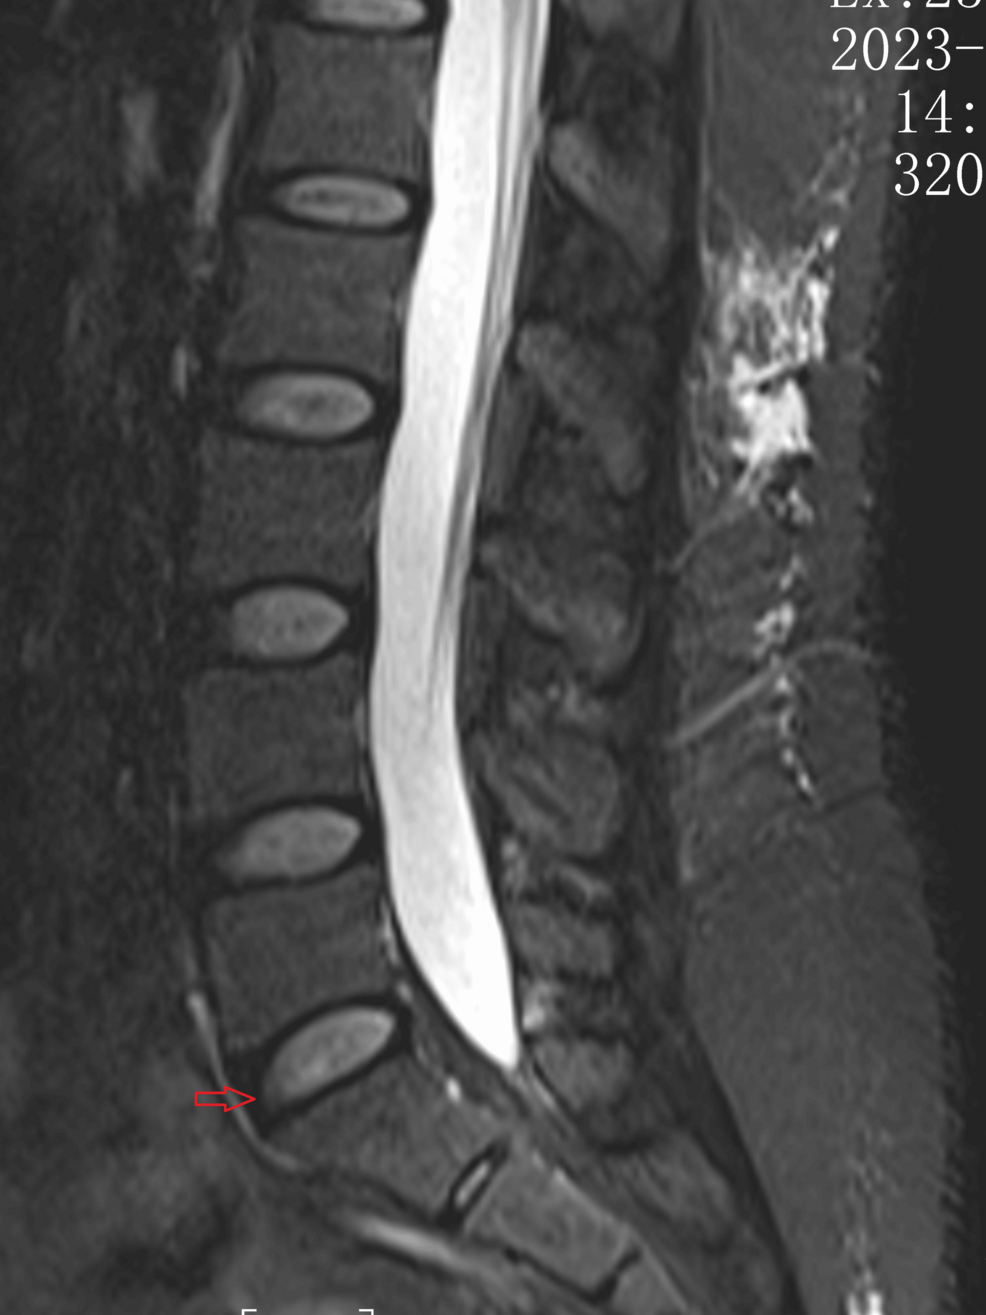

For decades, diagnosing gout relied heavily on joint aspiration – a painful and sometimes inconclusive procedure. Traditional imaging techniques like X-rays often miss early-stage gout or can be ambiguous, leading to misdiagnosis and delayed treatment. **Gout**, particularly when presenting in atypical locations like the spine (as demonstrated in the Curet case report), can be particularly challenging to identify. DECT, however, leverages the technology’s ability to differentiate between different tissue compositions based on their response to varying energy levels. This allows clinicians to visualize urate crystal deposits – the hallmark of gout – with unprecedented clarity, even in areas where traditional methods fall short.

Unlike standard CT scans that use a single X-ray energy, DECT utilizes two different energy levels. Uric acid crystals have a unique chemical composition that absorbs X-rays differently at these varying energies. This difference is then translated into a color-coded image, making crystal deposits readily visible to radiologists. This technique isn’t limited to gout; it’s also showing promise in identifying other crystal-related arthropathies, like calcium pyrophosphate deposition disease (CPPD).